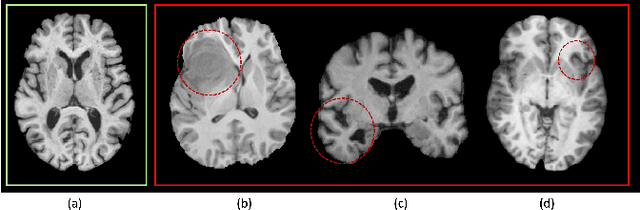

Abstract:The heterogeneity of neurological conditions, ranging from structural anomalies to functional impairments, presents a significant challenge in medical imaging analysis tasks. Moreover, the limited availability of well-annotated datasets constrains the development of robust analysis models. Against this backdrop, this study introduces a novel approach leveraging the inherent anatomical symmetrical features of the human brain to enhance the subsequent detection and segmentation analysis for brain diseases. A novel Symmetry-Aware Cross-Attention (SACA) module is proposed to encode symmetrical features of left and right hemispheres, and a proxy task to detect symmetrical features as the Symmetry-Aware Head (SAH) is proposed, which guides the pretraining of the whole network on a vast 3D brain imaging dataset comprising both healthy and diseased brain images across various MRI and CT. Through meticulous experimentation on downstream tasks, including both classification and segmentation for brain diseases, our model demonstrates superior performance over state-of-the-art methodologies, particularly highlighting the significance of symmetry-aware learning. Our findings advocate for the effectiveness of incorporating symmetry awareness into pretraining and set a new benchmark for medical imaging analysis, promising significant strides toward accurate and efficient diagnostic processes. Code is available at https://github.com/bitMyron/sa-swin.